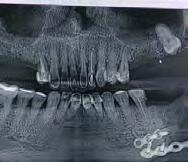

Figura 2. Imagen radiográfica inicial ósea en la mayoría de los dientes, con un defecto horizontal predominante y varios defectos en cuña en dientes aislados. Figura 3-6. Imágenes de la paciente, portadora de una prótesis removible para las ausencias dentarias presentes, que como vemos se encuentra completamente desadaptada además de con una estética poco adecuada.

2 3 5 7 4 6